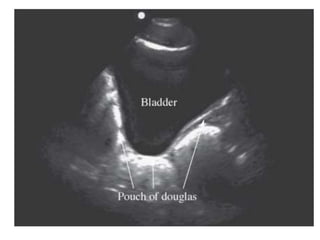

• Temuan Abnormal :

– Hemoperitoneum : regio anechoic antara VU dan

uterus atau uterus dan rektum

Suprapubik • Metode :(sagital) – Pasien dalam posisi supine – Indikator transduser mengarah ke kepala pasien – Transduser diletakkan diatas simfisis pubis, diarahkan ke pelvis – Identifikasi VU (triangular jika distensi), uterus (pear shaped), dan rektum

• 21.

• Metode :(transversal) – Indikator transduser diarahkan ke sisi kanan pasien – Transduser diletakkan 1-2 cm diatas simfisis pubis, dengan posisi menghadap ke pelvis – Identifikasi VU (rectangular jika penuh), uterus (oval hiperechoic) dan rektum

• Temuan Abnormal: – Hemoperitoneum : regio anechoic antara VU dan uterus atau uterus dan rektum